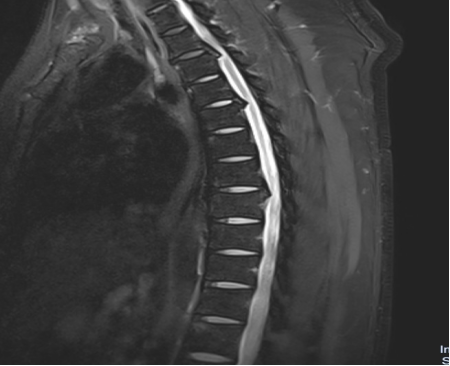

入院后,國文醫(yī)院骨科迅速組織多名專家會診,并為吳先生完善了頸椎及胸椎的 MRI 檢查。結(jié)果顯示,吳先生的頸椎及胸椎多階段嚴(yán)重椎管狹窄,脊髓壓迫超過 50%,情況十分危急。經(jīng)過骨科專家團(tuán)隊的綜合會診及評估,最終為他制定了一套個性化的治療方案,包括頸椎后路單開門椎管減壓頸椎融合內(nèi)固定術(shù),以及胸椎間盤切除伴椎管減壓胸椎植骨融合內(nèi)固定術(shù)。在完善術(shù)前檢查、確認(rèn)無手術(shù)禁忌后,骨科主任呂國福如期為吳先生實施了手術(shù)。

手術(shù)涉及頸椎及胸椎多個階段,操作難度極大。專家團(tuán)隊采用 “蠶食法” 減壓,分塊去除增生韌帶,最大程度減少對脊髓的損傷;同時運用椎弓根螺釘固定技術(shù),確保手術(shù)部位的穩(wěn)定性。

頸椎及胸椎管狹窄在 40 - 60 歲長期伏案工作者,以及有脊柱退變家族史者中較為高發(fā)。其典型癥狀表現(xiàn)為進(jìn)行性下肢無力、胸腹部束帶感、步態(tài)不穩(wěn)如 “踩棉花”。在治療選擇上,單階段狹窄可考慮微創(chuàng),多階段狹窄則開放手術(shù)更為徹底;若合并脊髓信號改變,建議盡早手術(shù)。